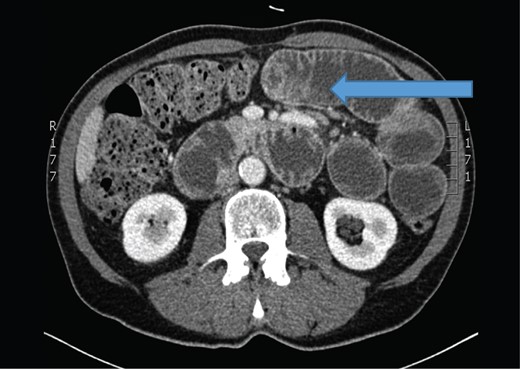

The abdominal computerized tomography showed small bowel obstruction with dilated small bowel loops (arrow).

In our case, small bowel obstruction was the initial clinical symptom for this patient. Primary lung cancer was suspected by a pathologist according to the immunohistochemical staining of metastatic lesion, that was taken from small bowel mesenterium during surgery. The diagnosis was later confirmed with chest CT, showing a large tumor mass in the left upper pulmonary lobe. The second abdominal CT confirmed diffuse small bowel metastases, that were found during emergeny surgery and metastases to both adrenal glands (stage IV).